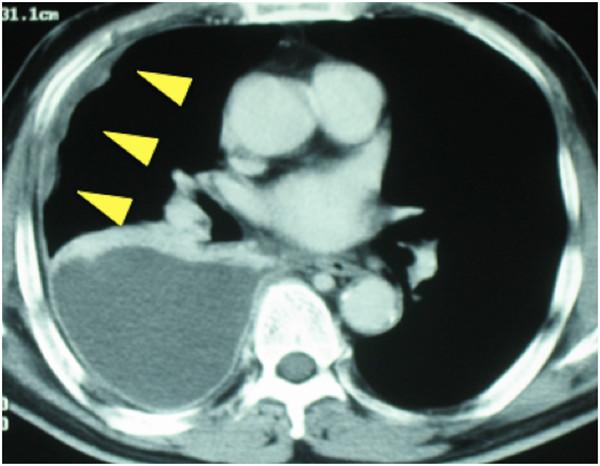

A 61-year-old Japanese man with a performance status of 1 due to chest pain was referred to our hospital. He had a history of asbestos exposure for approximately five years. A computed tomography scan showed diffuse extensive right pleural thickening with small nodular lesions, and video-assisted thoracoscopy revealed tumor invasion of the ipsilateral chest wall muscles. The histopathologic findings were consistent with a diagnosis of malignant pleural mesothelioma (sarcomatoid type). The tumor was diagnosed as being stage cT3N0M0. Our patient refused any invasive therapies including surgery and radiotherapy, and was therefore treated with hyperthermia and systemic chemotherapy with agents such as cisplatin and irinotecan. He underwent three hyperthermia sessions and a single course of chemotherapy without any severe complications. One month after treatment, a follow-up computed tomography scan showed no definitive abnormality in the thoracic space. Our patient has subsequently survived without any evident disease for more than seven years.

一名61岁的日本男性因胸痛导致身体状况评分为1,被转诊至我院。他有大约五年的石棉接触史。计算机断层扫描显示右胸膜弥漫性广泛增厚并伴有小结节病变,电视辅助胸腔镜检查发现肿瘤侵犯同侧胸壁肌肉。组织病理学检查结果与恶性胸膜间皮瘤(肉瘤样型)的诊断一致。肿瘤被诊断为cT3N0M0期。我们的患者拒绝包括手术和放疗在内的任何侵入性治疗,因此接受了热疗和使用顺铂、伊立替康等药物的全身化疗。他接受了三次热疗疗程和一个化疗周期,未出现任何严重并发症。治疗一个月后,随访计算机断层扫描显示胸腔内无明确异常。我们的患者随后已无明显疾病存活超过七年。